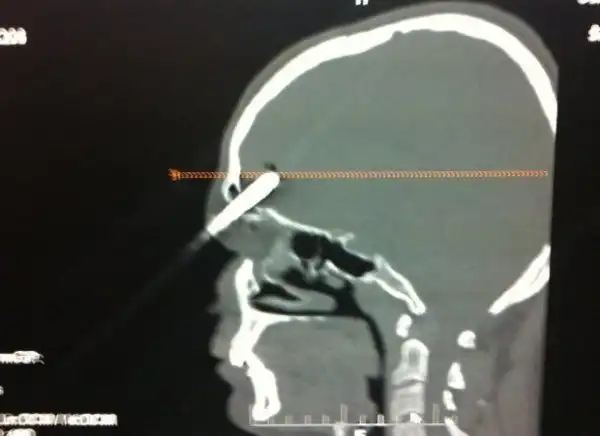

25-летний поляк трудился у себя в саду, когда потерял равновесие и упал на инструменты. Поднявшись и придя в себя он посмотрел в зеркало и обнаружил, что у него из головы торчит отвертка. Мужик не стал суетиться, а просто достал сигарету, закурил и отправился к соседу, чтобы тот помог ему добраться до больницы. Как оказалось, отвертка вошла в мозг на пять сантиметров, но очень удачно, поэтому инструмент без труда извлекли, а дырку залатали.